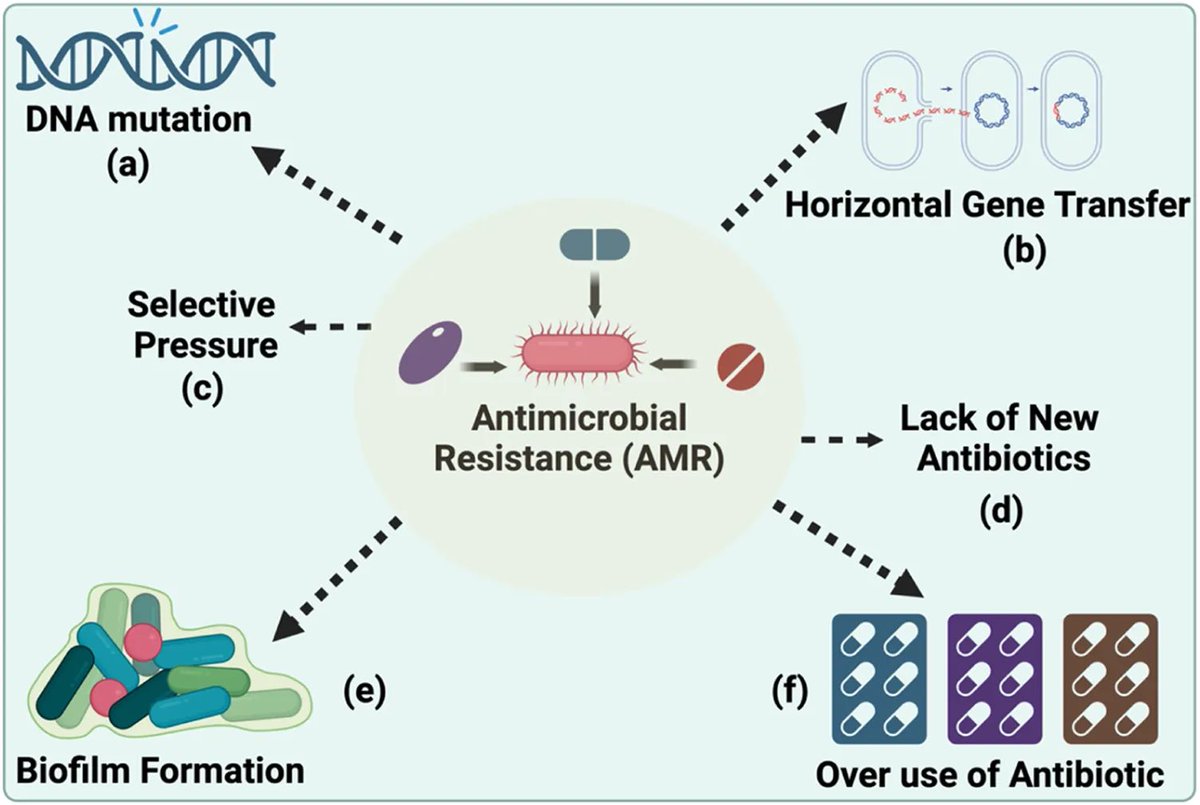

Si te dicen q un #NUEVO antibiótico NO TIENE RESISTENCIAS🆕💊…. no te lo creas! Frontiers - Microbiology bacteria congelada hace 5000 años🥶…ya era R a 10 ATB📸. Los ATB provienen de la naturaleza y existen mecanismos en ella para combatirlos Frontiers - Microbiology 🔗🆓frontiersin.org/journals/micro…